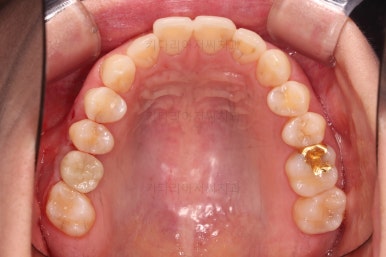

치료 종료시의 모습인데요.

임플란트가 잘 들어갔고 아래 앞니도 원하는 모습으로 잘 배열이 되었습니다.

부산치아교정비용 전후 비교해 볼게요.

치료기간은 임플란트의 안정성 때문에 길어지긴 했으나 사실상 내원횟수는 그리 많지 않으셨고, 교정장치가 눈에 보이는 기간은 7개월정도 밖에 안되었기 때문에 크게 문제되지는 않았던 것 같습니다.

여러 가지가 다 잘 마무리 되었습니다.

이상 아래 앞니 부분교정 및 임플란트를 위한 어금니 부분교정 이후 임플란트까지 완성한 치료사례였고 부산치아교정비용과 가격도 대략 알아보는 시간이었습니다.